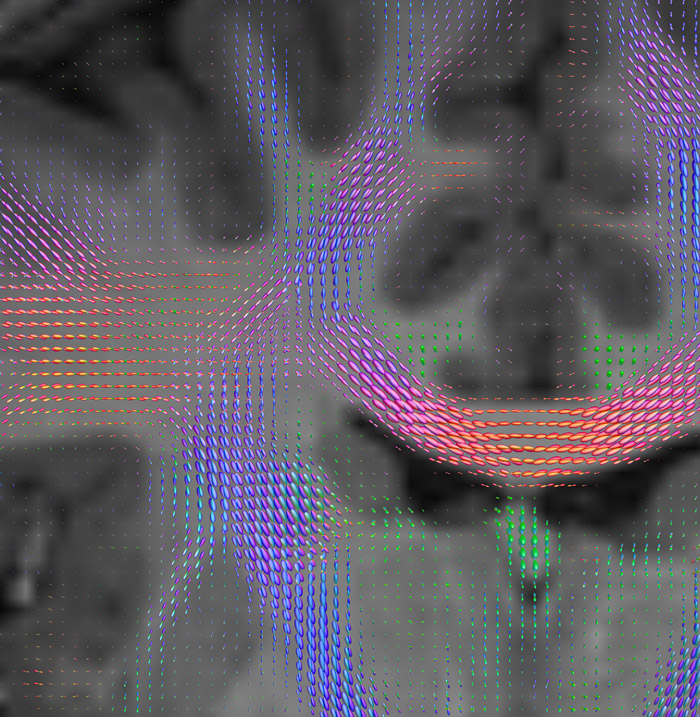

CSD of multishell DWI results in the white matter FOD at each voxel. Unlike the conventional diffusion tensor model, this approach enables accurate modeling of multiple fiber populations within a single voxel.

Crossings of the corpus callosum, corticospinal tracts, and the superior longitudinal fasciculus are shown.

Crossing fibers of the corpus callosum bordered by the superior longitudinal fasciculus as well as within in the pons.

All images were created from the same acquisition in a child using Ingenia 3.0T CX and 32-channel dS Head coil. Diffusion data was acquired at b-values 0, 500, 1000, 2000, 3000. The use of high b-values (3000 s/mm2) effectively suppresses extra-axonal water signal and provides high angular resolution.

CSD: constrained spherical deconvolution

DEC TDI: directionally encoded color track-density imaging

DTI: diffusion tensor imaging

DWI: diffusion-weighted imaging

FOD: fiber orientation density

Data processing was performed using open source software. Fiber tracking was performed using the MRtrix package (J-D Tournier, Brain Research Institute, Melbourne, Australia, https://github.com/MRtrix3/mrtrix3), Tournier et al. 2012. DEC TDI based on F Calamante et al 2010.